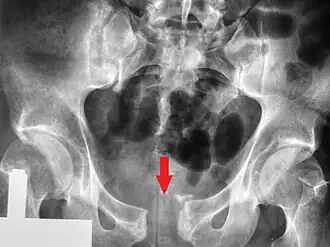

| Radiografia pélvica em que se observa fratura aberta | |